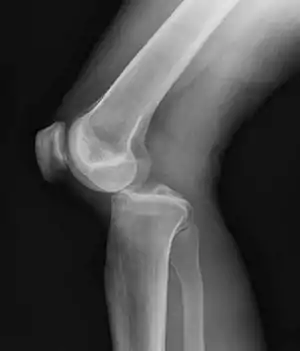

| Plain lateral X-ray of the left knee showing a posterior knee dislocation[1] | |

Plain X-rays, CT scan, ultrasonography, or MRI may help with the diagnosis.[2][10] Findings on X-ray that may be useful among those who have already reduced include a variable joint space, subluxation of the joint, or a Segond fracture.[5]

They may be divided into five types: anterior, posterior, lateral, medial, and rotatory.[4] This classification is based on the movement of the tibia with respect to the femur.[10] Anterior dislocations are the most common, followed by posterior dislocations.[2] They may also be classified based on what ligaments are damaged.[2]